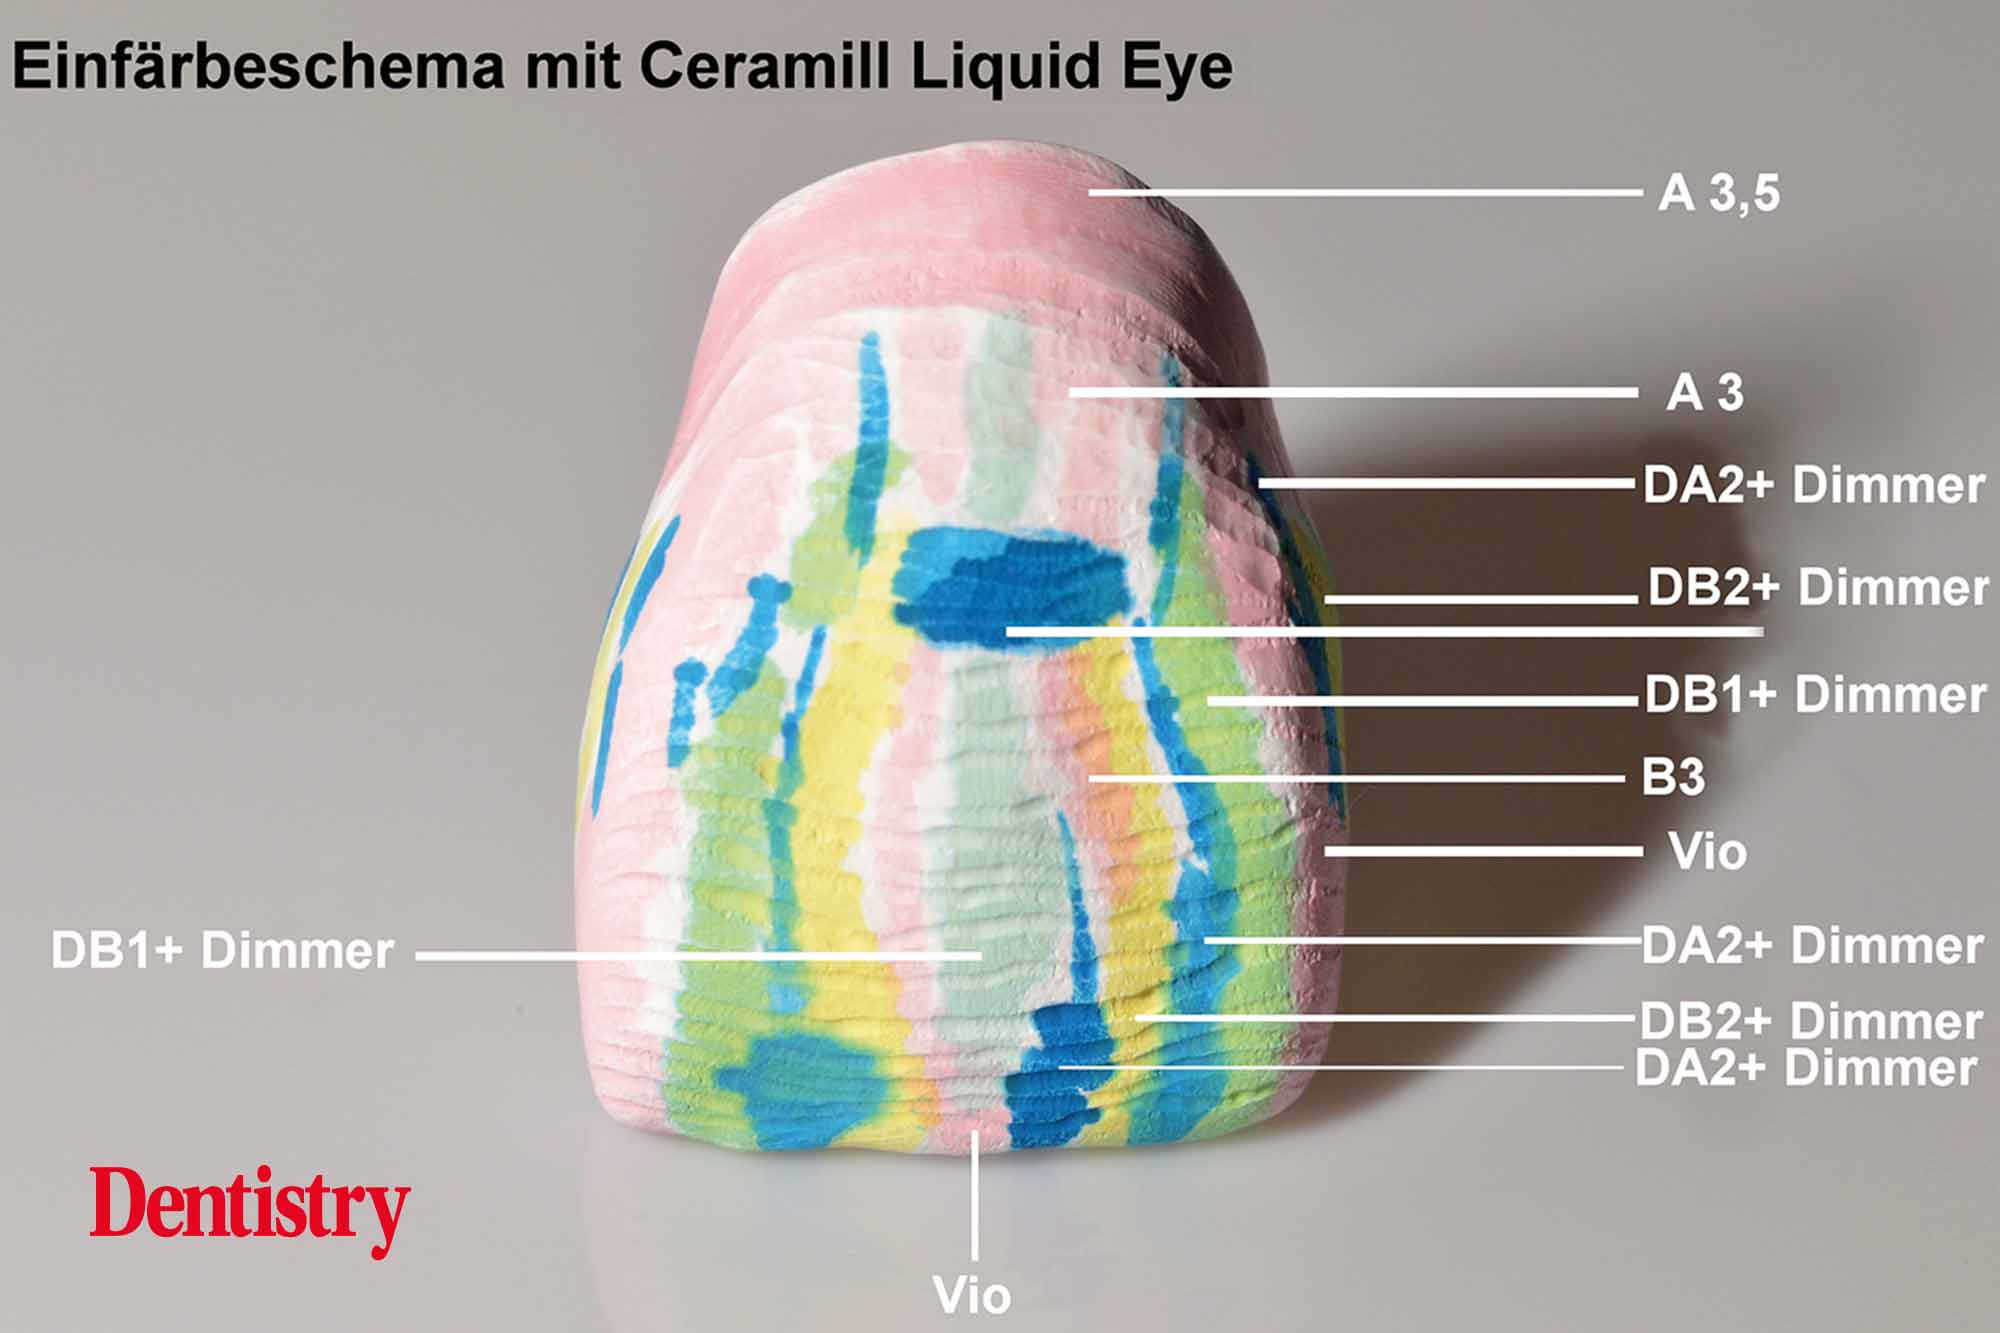

The milled Ceramill Zolid FX (super high translucent) monolithic zirconia maxillary crowns were polished and then individually coloured with brushed-on Ceramill liquid colour before sintering. As opposed to lithium disilicate, it can be coloured before sintering. The advantage of this is that it produces a similar chroma to that of natural teeth.

The colouring liquids were available in all VITA classical shades and were applied in an alternating fashion. Liquid colours Dentin A1 + Dimmer, Dentin A2 + Dimmer, Dentin B1 + Dimmer (30% to 70%) and Violet were applied in a strategic way with dentin colours B3 and A3.5 being used in the fissure and marginal areas (Figures 14 and 15).

The crowns were immersed for 10-15 seconds in the dentine-coloured Ceramill Dimmer liquid.

Depth effect, due to the transparency effect of the Ceramill liquids, was achieved using alternating NB/C/D liquids, brown/orange liquids for fissures and interdental regions, grey/blue shade modifier liquids, and Ceramill Liquid Eye.